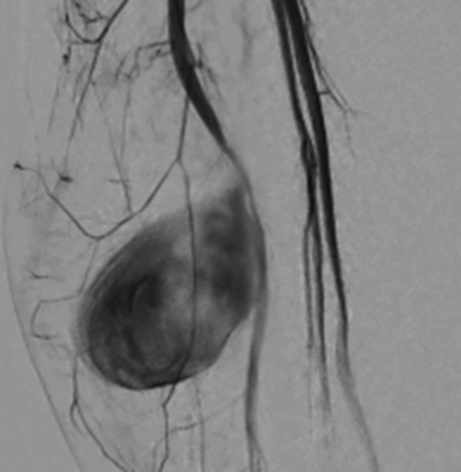

Explanation: The angiographic image shows a well-defined contrast-filled outpouching arising from the inferior gluteal artery, consistent with a pseudoaneurysm. Unlike active bleeding, which typically appears as diffuse extravasation without a defined border, a pseudoaneurysm forms a sac-like structure due to a breach in the arterial wall with blood contained by surrounding tissue. In this case, endovascular coil embolization was the definitive treatment, effectively occluding the lesion and preventing further hemorrhage.

Angiographic Imaging

Arterial angiography was performed, revealing a pseudoaneurysm of the inferior gluteal artery. The lesion was successfully treated with percutaneous coil embolization.

Ultrasound imaging revealed a gluteal hematoma accompanied by a vascular lesion demonstrating the characteristic "yin-yang" sign. Spectral Doppler imaging showed a "to-and-fro" waveform, suggestive of a pseudoaneurysm.

On CT imaging, a nodular hyperdense lesion was observed within the gluteal region during the arterial phase, which gradually faded during the venous phase, also indicative of a pseudoaneurysm.

Gluteal hematoma and inferior gluteal artery pseudoaneurysm